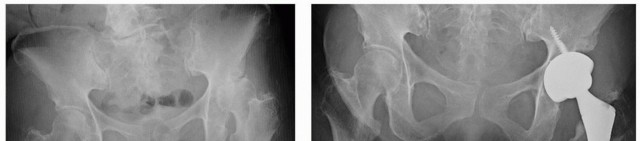

التهاب المفاصل الالتهابي (Inflammatory Arthritis)

مثل التهاب المفاصل الروماتويدي، يمكن أن يسبب تدميرًا واسع النطاق لمفصل الورك. في هذه الحالات، يمكن أن يوفر التثبيت بدون أسمنت حلاً مستقرًا وطويل الأمد، مع الأخذ في الاعتبار الخصائص البيولوجية للعظم المتأثر بالالتهاب.

كسور عنق الفخذ (Femoral Neck Fracture)

في بعض حالات كسور عنق الفخذ، خاصة لدى المرضى الأصغر سنًا أو الأكثر نشاطًا، قد يكون استبدال مفصل الورك الكلي باستخدام مكونات غير مثبتة هو الخيار الأفضل لاستعادة الوظيفة الكاملة وتقليل مخاطر المضاعفات المستقبلية.